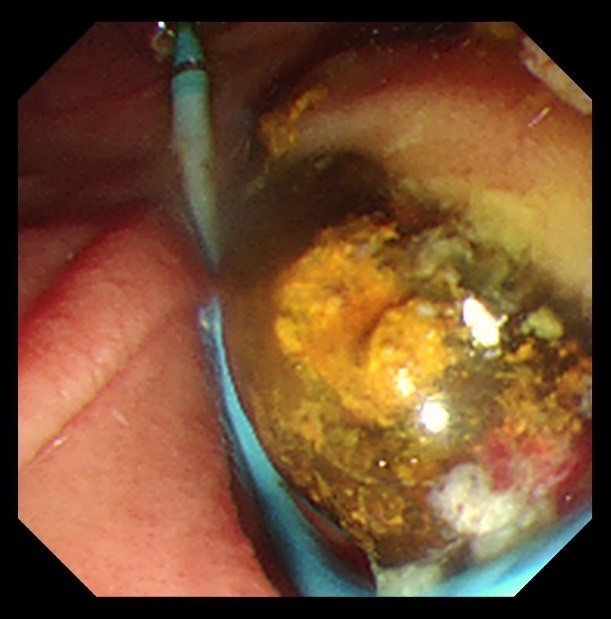

苏大附四院ERCP团队在手术中看到陈大爷的胆总管在结石的影响下已经宽达13mm,结石大小11*10mm,将十二指肠乳头切开并扩张后用取石球囊把结石取出,置入胆管支架使胆汁充分引流,顺利解除了胆道梗阻。

扩张取石